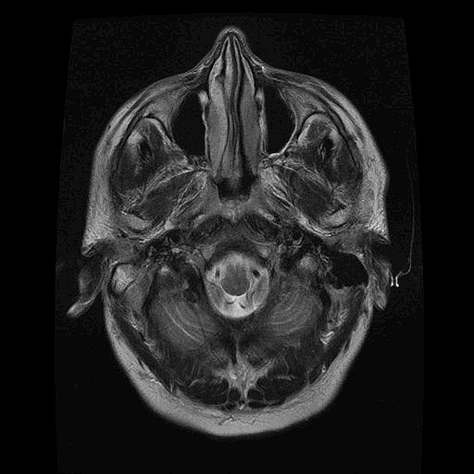

A PET scan is organised a few days later, at St Barts Hospital, in the shadow of St Paul’s. The body is flooded with a tracer radioactive fluid, after which you are locked into a lead-lined box for three-quarters of an hour to allow it to bake in. The scanner then detects where the tracer has been absorbed by cell growth anywhere in the body it is directed, producing reams of flowing light captured to film, copies of which—scans of my own body—are used throughout this post.

The moment I saw the very first scan the doctors showed me (bottom right, above: an MRI, rather than PET, as it happens)—on a small monitor wheeled into my cubicle at the Homerton—seemed to say everything at once. As I turned my head to look at the image of my brain on the monitor, I glimpsed also the tattoo on my left arm suddenly aligned with it (bottom left)—a tattoo of a bhikkhu meditating in flames, inked twenty years earlier, with the bhikkhu meditating as descibed in the Buddha’s Adittapariyaya Sutta (Fire Sermon)—such that the tattoo of the bhikkhu and the scan of the brain, aligned properly. One presaged the other by years, holding out its hand to the other. They reflected each other so neatly, with the tumour in the cerebellum showing up as the red-orange fire bursting through from within, which the bhikkhu sits through.

The wrinkled surface of the cerebral cortex in the scan echoed the Bhavachakra—the wheel of Saṃsāra, of cyclical existence (“Saṃsāra… is a Sanskrit word that means ‘wandering’ as well as ‘world’, wherein the term connotes ‘cyclic change’ or, less formally, ‘running around in circles’)10—against which the bhikkhu rests in the tattoo. Here is an image, not only of that empty time turning that we have talked of, of cyclical return and, dare I say it, reincarnation (though in this formulation, reincarnation is mere repetition, as in the ‘natural’ repetition of pagan society). In the original Fire Sermon, the argument is that the bhikkhu must free themself from the grasping tyranny of the senses. We, on the other hand, will be moving in the other direction. In any case, this combined image almost made me fall out of bed.

On seeing further scans, I recognised, eg., my rib cage as something indeed very much like the frame of Israel’s tents (above, top left), beaming on the shore of the infinite (Blake), but also, in the twisting images of the torso, I am struck by the sprawling energies at play, unleashed by disease. No longer is there the assumed underlying durable person, sealed away from the totality, cybernetically establishing their personal border by fending off and repurposing the chaos, sickness and disorder without. Instead, raw energies start to coalesce, turning Urizenic, mechanical rigidity into flashes, streaks and pulses of contending light.